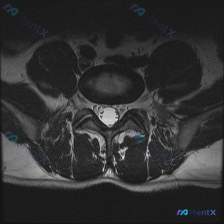

本次提供的是一张腰椎MRI轴位T2加权像,临床预设方向为椎间盘病变,需要分析影像可见病变,并梳理后续诊断思路。

- 序列与解剖识别:这是典型的腰椎T2加权轴位像,脑脊液呈高亮信号,能清晰分辨椎体后缘、椎间盘、椎管、硬膜囊、小关节、黄韧带和椎旁肌肉结构

- 椎间盘层面:椎间盘后缘形态基本正常,没有看到明显的局限性突出或脱出;髓核信号也没有明显降低,不存在严重的退行性脱水改变

- 椎管与侧隐窝:椎管形态、前后径、横径都没有明显狭窄,双侧侧隐窝空间充足,没有因为椎间盘突出或上关节突增生导致的狭窄;硬膜囊形态圆润,没有受压变形

- 骨性结构与韧带:双侧小关节关节面平整,关节间隙没有狭窄,也没有关节积液或滑膜囊肿;黄韧带没有明显肥厚或钙化;椎体后缘轮廓光滑,没有明显骨赘压迫椎管

- 神经与软组织:椎管内马尾神经形态自然,没有移位或聚集,提示没有受压;双侧椎旁肌肉信号正常,没有萎缩、脂肪浸润或异常水肿

影像综合结论:在这张单轴位扫描层面上,没有观察到明确的腰椎间盘突出、椎管狭窄或严重的结构性退行性病变,和预设的「椎间盘病变」不完全符合。当然也要说明,单张轴位片没法评估矢状面的椎间孔病变、Modic改变或腰椎滑脱,需要结合完整影像判断。